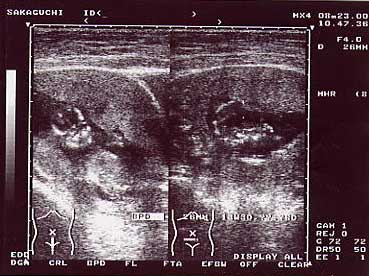

◆写真◆

ベイビーのエコー写真です。